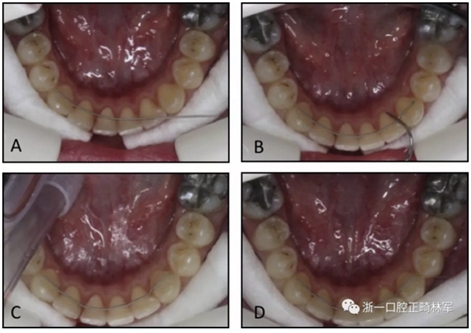

圖2. 第二組,在沒有石膏模型的情況下制備極軟的保持弓絲:A,極軟的保持弓絲與左側(cè)尖牙粘接; B-D,然后弓絲被動地適應并粘接到其他牙齒。

在第二組中,保持器直接粘結(jié)。首先,用與第1組相同的粘接劑將極軟的保持弓絲粘接到左側(cè)尖牙上,然后將弓絲被動地與其他尖牙和切牙的舌側(cè)表面相適應。極軟弓絲使臨床醫(yī)生能夠使用手持儀器輕松彎曲保持器(圖2)。下頜切牙和另一個尖牙用相同的粘接劑底漆和糊劑粘接。所有的保持器都由同一個擁有超過2年臨床經(jīng)驗的研究員(F.G.)粘接。在兩組拔牙患者中,保持器達到了第一前磨牙。兩組上頜牙弓均采用壓模保持器。